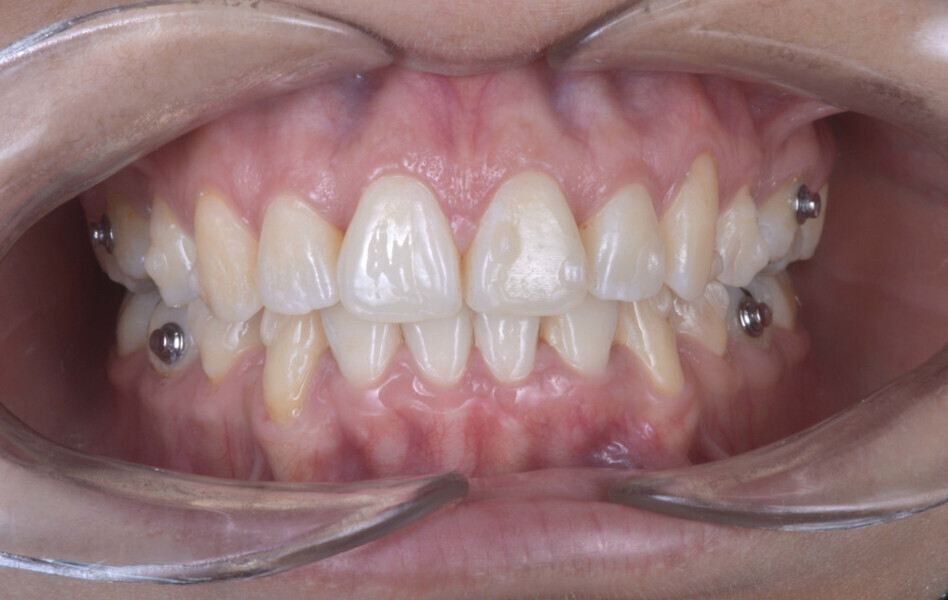

Before the aligner treatment began, the maxillary and mandibular second premolars were extracted to create space. With orthodontic treatment, distalisation of the anterior teeth was achieved by employing maximum mandibular anchorage and moderate maxillary anchorage (Figs. 5–7). At the end of the treatment, a stable bilateral Class I occlusion had been achieved, as well as normal inclination and retrusion of the anterior teeth, consequently improving the profile (Figs. 8–10).

At the end of the treatment, the patient showed a significant improvement in her profile thanks to the orthodontic treatment (Fig. 11) and an improvement in her facial shape thanks to the injection of botulinum toxin into the elevator muscles (Fig. 12). She also had a decrease in bruxism and its symptomatology thanks to the combination of both treatments.